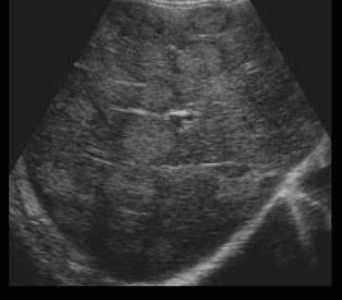

>5cm hcc sono finding (3) 미만형 간세포암(diffuse type)

간 전체가 결합조직으로 둘러싸인 무수히 작은 종양결절로 뒤바뀐 형태를 말한다. 침윤성 발육으로 인해 정상조직 부위와의 경계는 불분명하다. 간경변증의 거친 간실질상과의 감별은 어렵다. 하지만 문맥 내 종양혈전(portal vein thrombosis)의 존재로 인해 미만성 간세포암이 발견될 가능성이 매우 높지만 문맥 내 종양혈전은 문맥을 따라 간전이를 일으키므로 대장암, 위암 등의 간전이에서도 볼 수 있다. 예후가 매우 불량한 편이다.